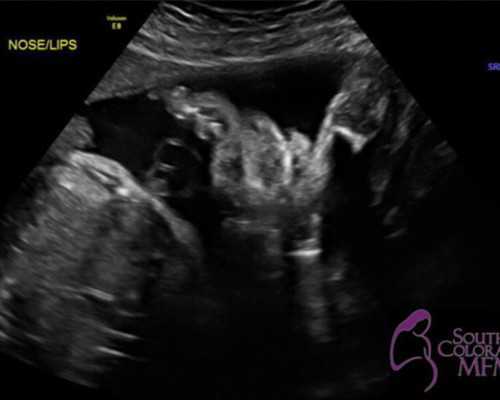

B超的检测原理是:B超的检测性别需要等到胎儿成型好,然后才能通过超声波然后来检测胎儿,根据不同性别的胎儿的外表是存在差异性的,所以超声波扫描出成型的胎儿外表判断性别。这也是为什么B超检测需要这么久的怀孕时长原因。